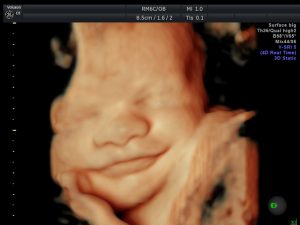

3D/4D-ultralyd

3D Ultralyd

Copyright GE Vingmed Ultrasound AS / Images made by Dr. Benoit